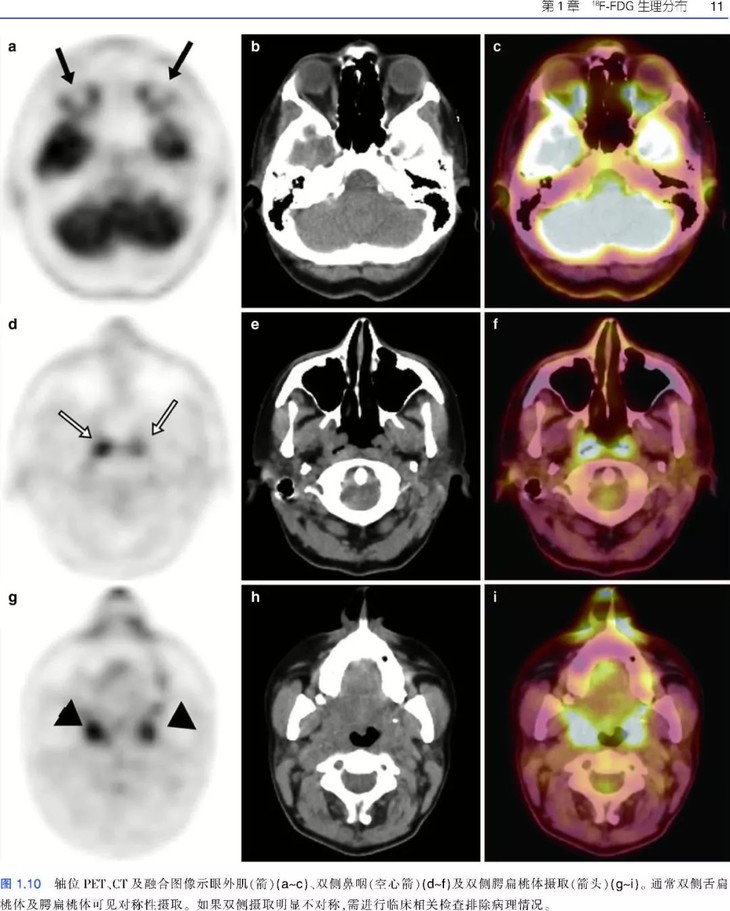

《肿瘤PET/CT成像图谱:病例解析》PET/CT扫描仪的出现,意味着功能代谢信息和解剖数据的融合,开创了医学领域的新纪元,特别是肿瘤学领域。自从PET/CT出现于研究中心,就成为肿瘤影像学中不可或缺的工具。《肿瘤PET/CT成像图谱:病例解析》涵盖了很多关于恶性肿瘤18F-FDG PET/CT诊断和治疗的临床病例。全书共两部分内容,第1部分为FDG PET/CT基础知识,包括18F-FDG的生理分布、正常变异、良性病变和技术伪影。第2部分涵盖了大量临床肿瘤病例,包括常见和罕见表现。每个病例都按照简要病史、影像表现描述、影像表现解释的顺序进行论述,最后是由相关文献支持的学习要点。本书中的所有病例均经组织病理学证实。本书适合核医学、放射学、肿瘤学、肿瘤放射学和核医学技术专业的住院医师和执业医师阅读。

• 涵盖全身各部位肿瘤的临床病例和大量PET/CT图像;

• 图片清晰,内容描述简明扼要,便于读者阅读和理解;